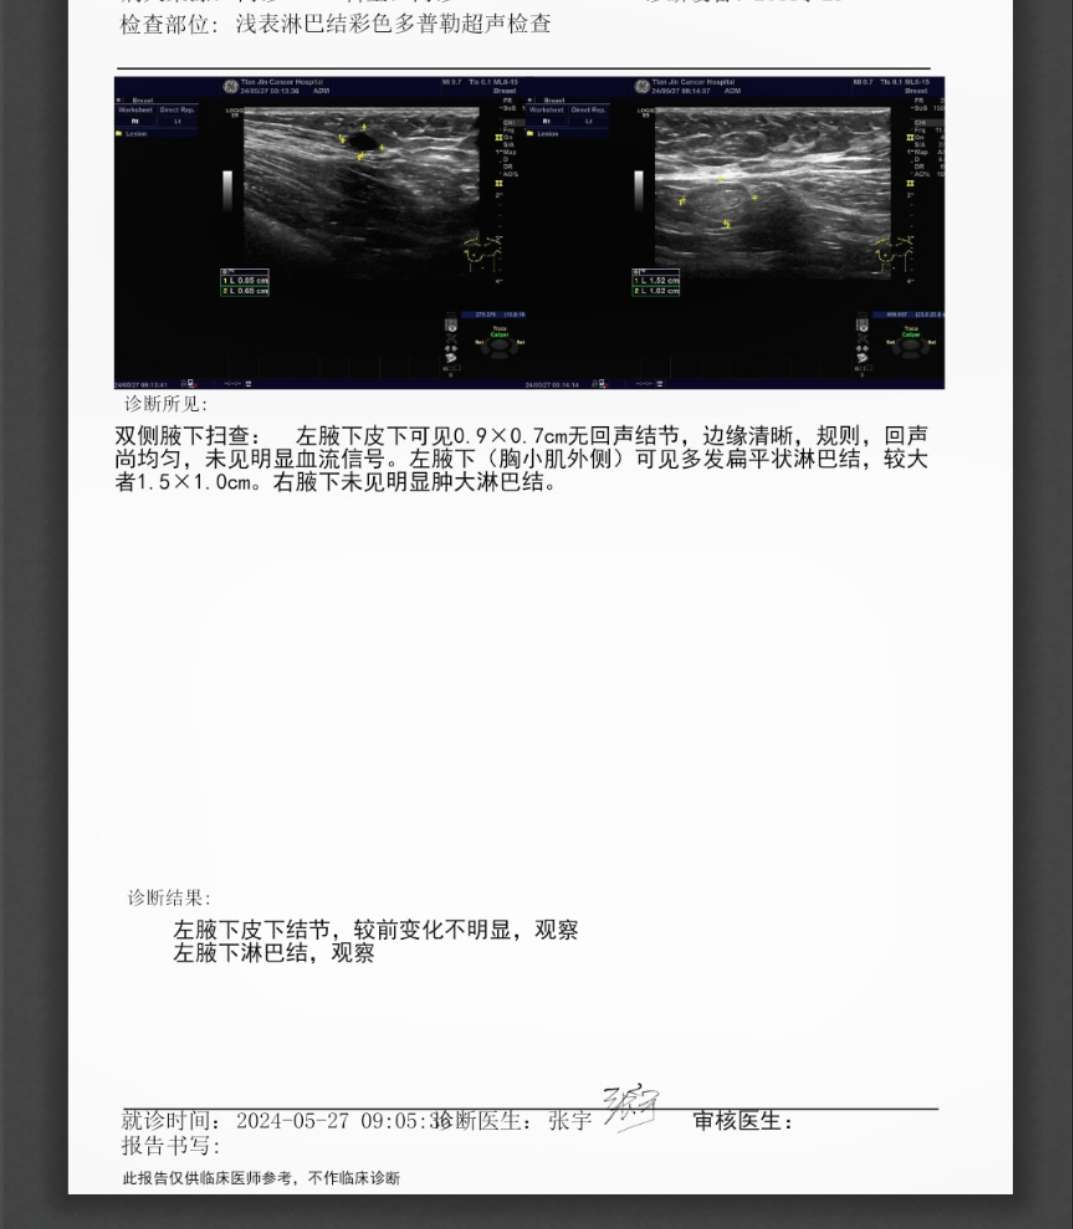

这是刚复查的

2024-05-27 12:13:38 有用(0)